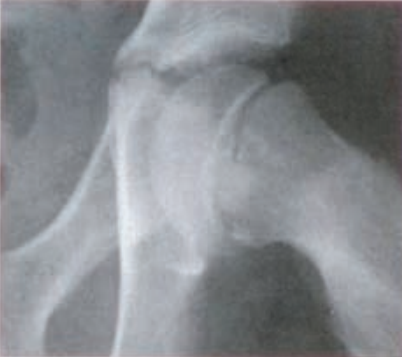

Na rentgenogramie przedstawione jest złamanie Saltera-Harrisa typu

Ilustracja do pytania 19

A. II odcinka bliższego kości piszczelowej.

B. V czwartej kości śródręcza.

C. I ześlizgnięcie bliższej nasady kości udowej lewej.

D. III nasady dalszej kości piszczelowej.